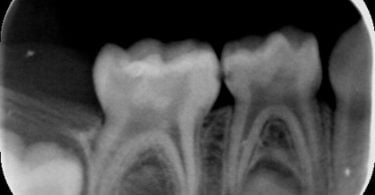

Foi realizado um exame clínico e radiológico inicial (fig. 1 a 3), tendo sido diagnosticada, entre outras lesões de cárie, uma lesão de cárie profunda com atingimento pulpar no segundo molar temporário inferior direito (fig. 3). Foi proposta a realização de uma pulpotomia com agregado trióxido mineral (MTA) e a colocação de uma coroa pré-formada. As várias possibilidades restauradoras foram apresentadas e discutidas com os pais, que decidiram optar pela colocação de uma coroa pré-formada de zircónia, por motivos estéticos.